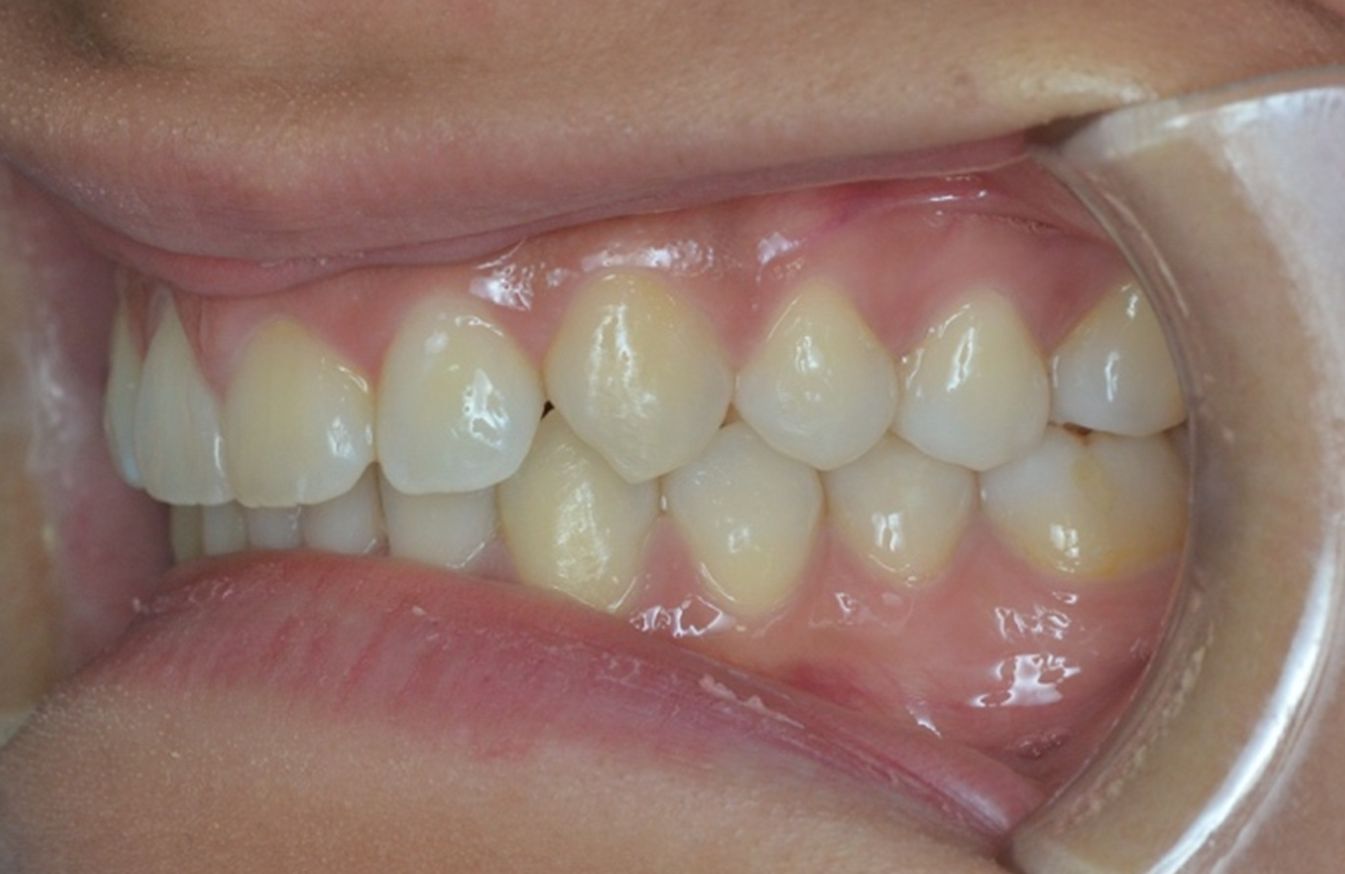

A continuación, mostramos el caso de una paciente adulta con clase II ósea y dentaria.

Con Ortodoncia Invisible, y gracias a la cooperación de la paciente, conseguimos este resultado y, lo más importante de todo, que la paciente sonría sin complejos.